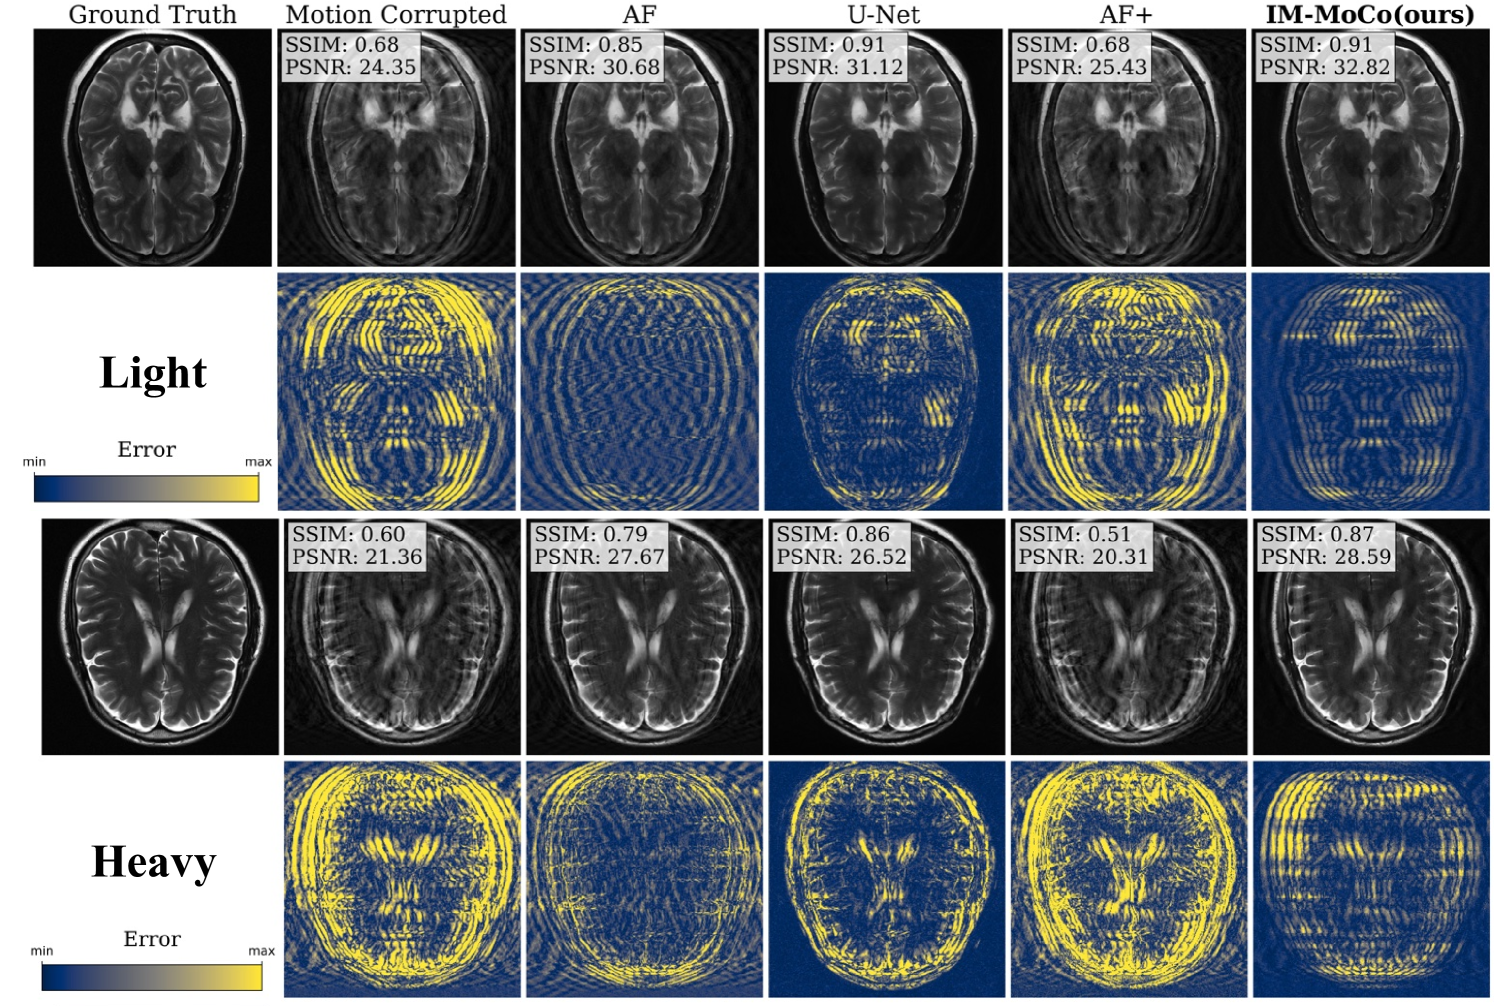

Refer to caption

Figure 4: The visualization shows the worst results of motion-corrected images of our IM-MoCo pipeline besides motion-corrupted, ground truth, and comparison methods. The first and third rows show the light and heavy correction results, respectively. The second and fourth rows show the residual error images.

Figure 5: The visualization shows the best results of motion-corrected images of our IM-MoCo pipeline besides motion-corrupted, ground truth, and comparison methods. The first and third rows show the light and heavy correction results, respectively. The second and fourth rows show the residual error images.